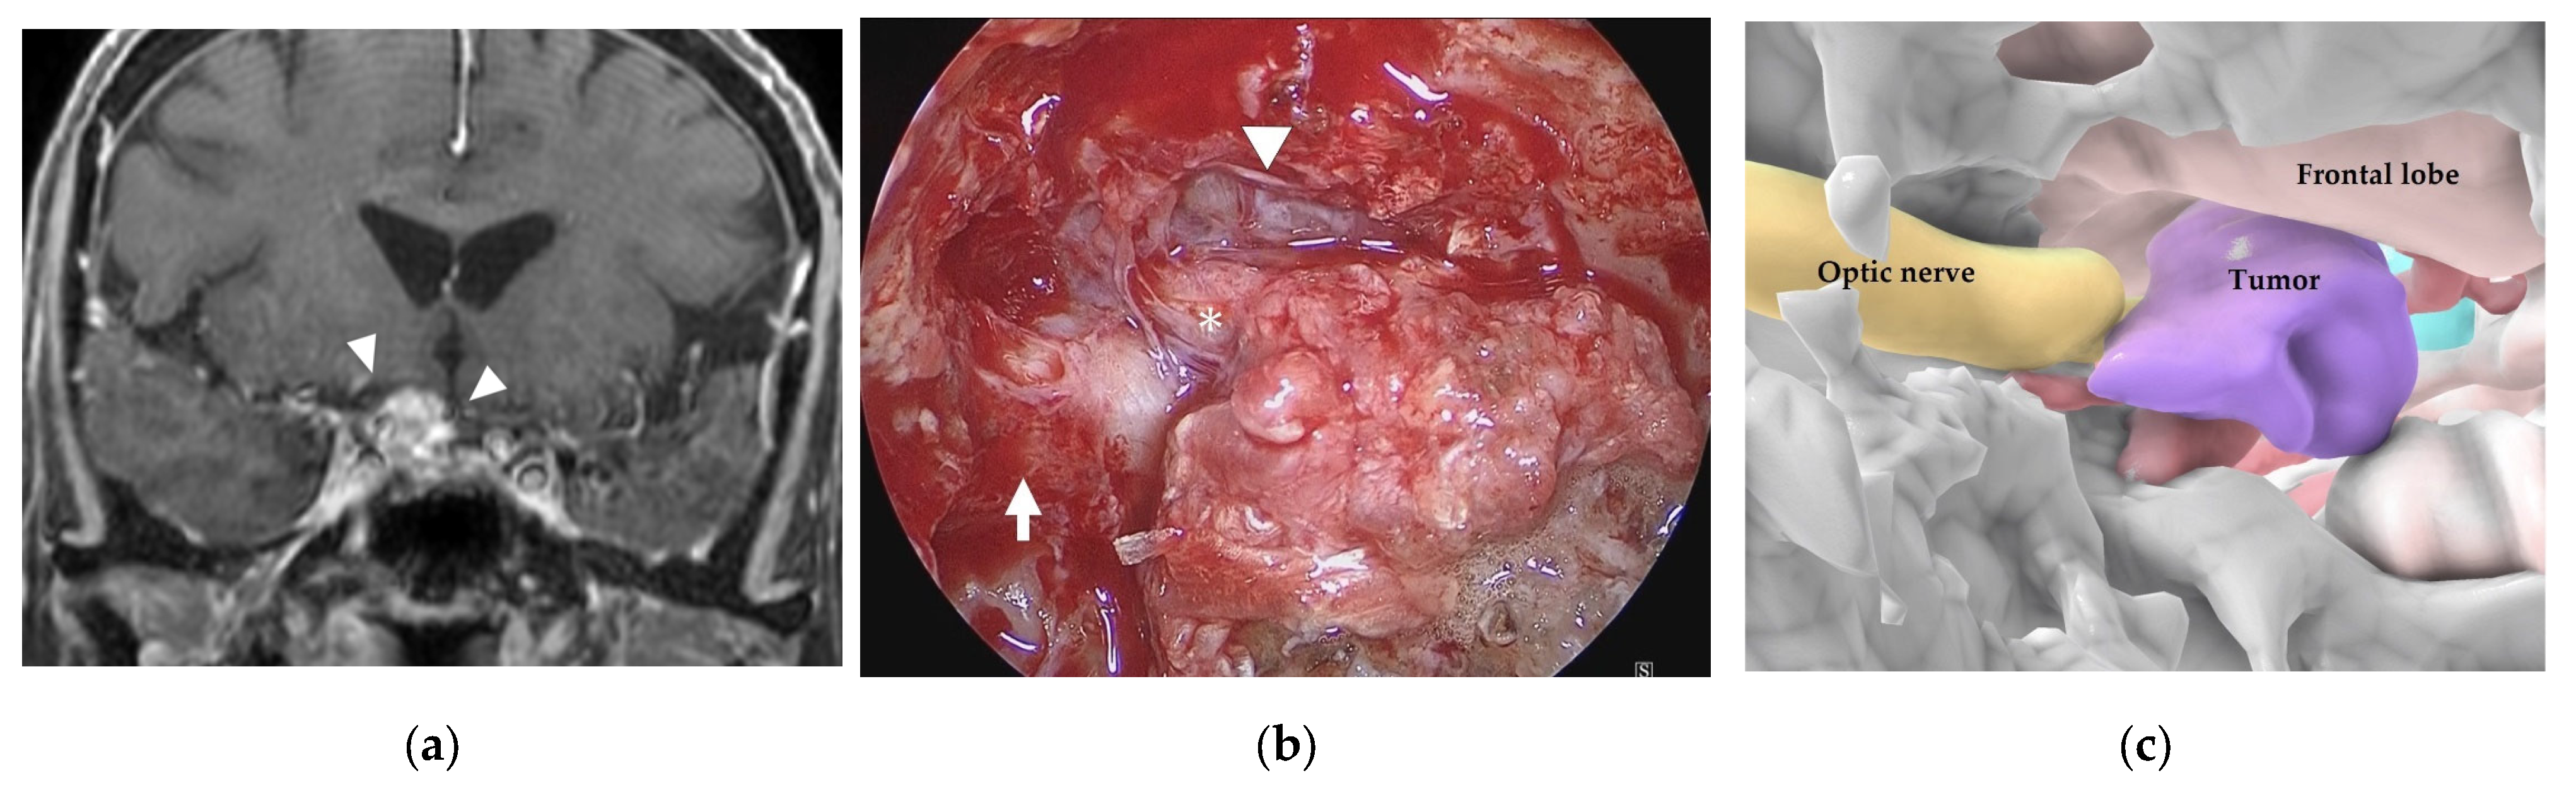

3.2. Illustrative Case 2 (Case 9)